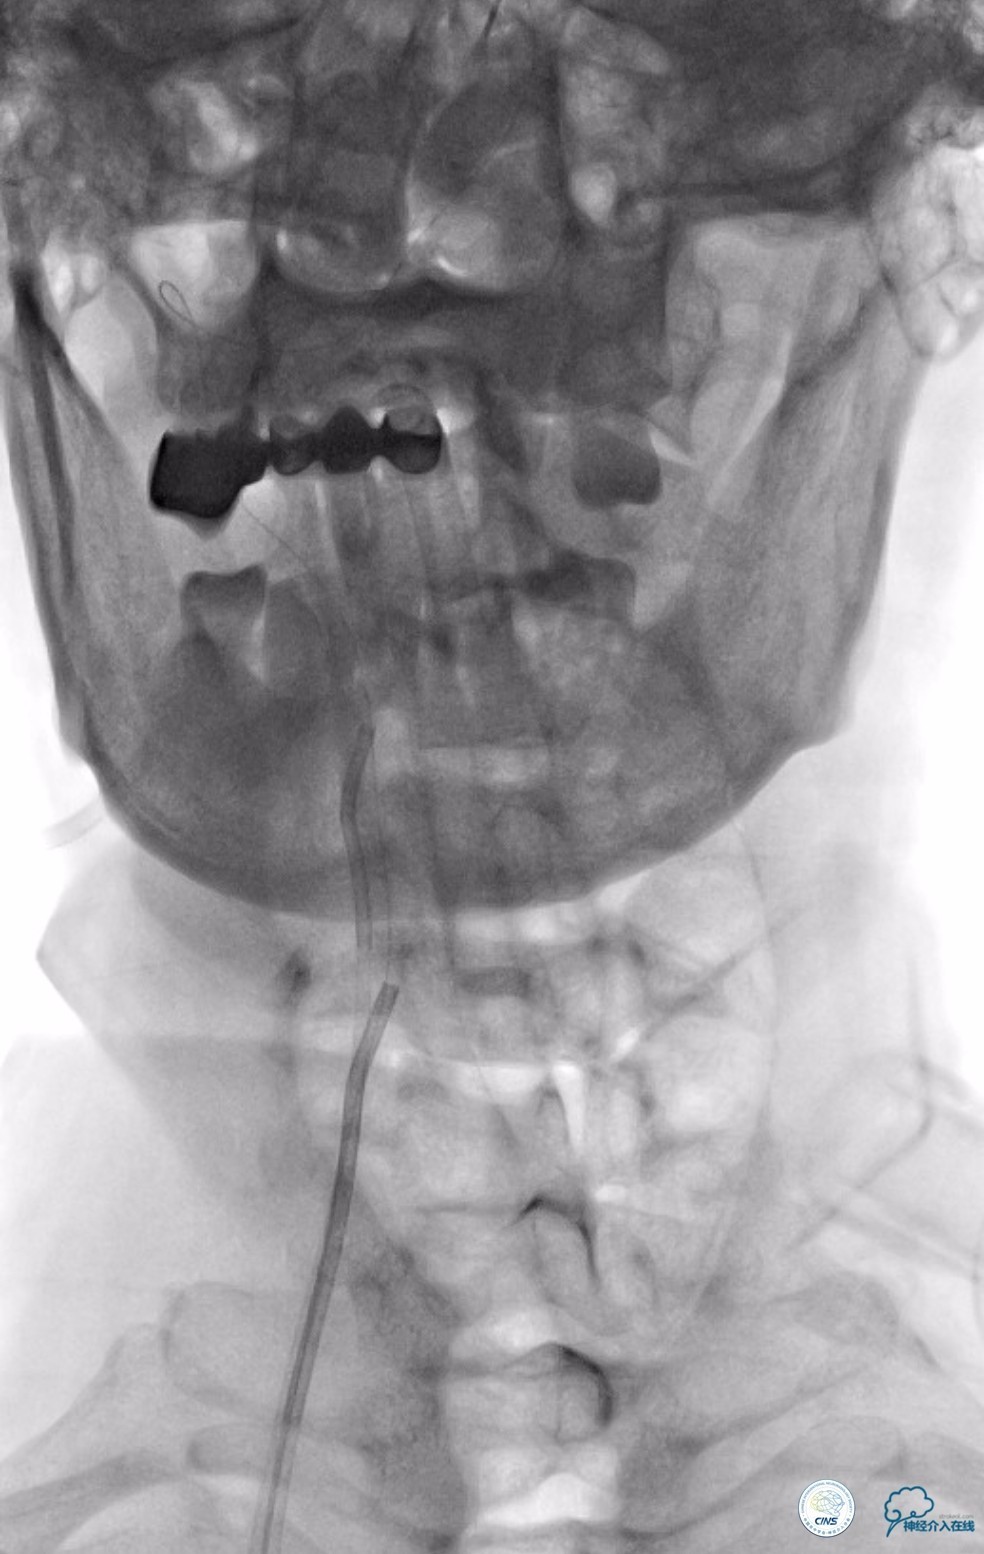

动脉粥样硬化狭窄合并动脉瘤的处理,因治疗狭窄和栓塞动脉瘤的两套系统常需要并列使用,事先要考虑所用导引导管是否能完全容纳两套系统,如本例8F导引导管到位困难,故只能改用两套系统完成治疗(图14)。

图14